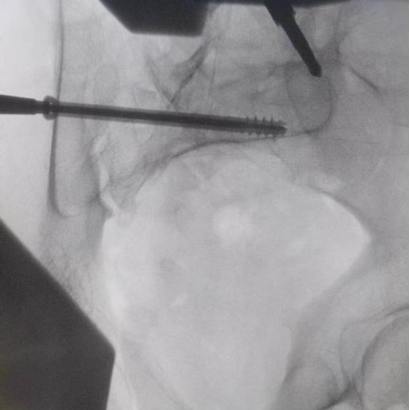

據(jù)了解,患者37歲,為高墜傷患者,入院合并顱腦挫傷、盆腔臟器出血、骨盆骨折多發(fā)傷患者。為最大限度降低手術(shù)風險,同時給予患者滿意的手術(shù)療效,術(shù)前綜合評估患者病情,擬定行“天璣機器人”輔助定位下骨盆骨折微創(chuàng)手術(shù)。2月13日10時,手術(shù)正式開始。拉薩市人民醫(yī)院采集患者術(shù)中二維影像,通過骨科手術(shù)機器人擬定螺釘打入位置方向后,吳宏華主任完成手術(shù)設(shè)計,成功為該患者置入了一顆高難度骶髂螺釘,出血5ml,切口1cm。術(shù)后圖像顯示,螺釘位置及方向完全符合手術(shù)規(guī)劃,沒有一絲偏差,手術(shù)最終獲得圓滿成功。

圖為透視下見置入的骶髂螺釘,位置、長度精準,無絲毫偏差